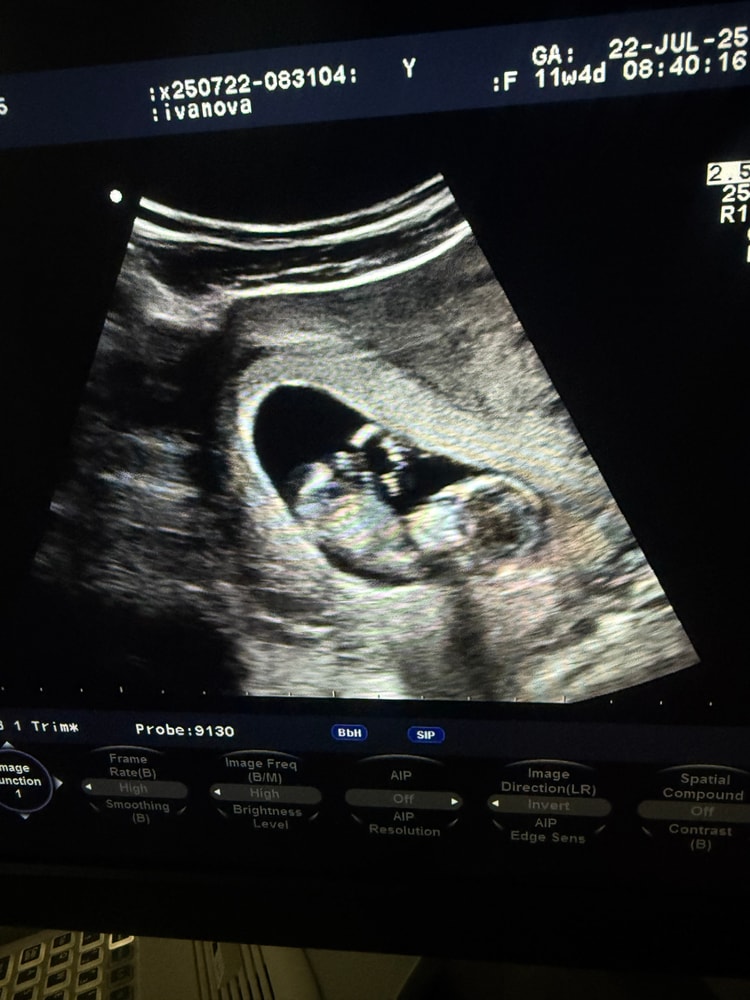

Пол на первом скрининге

Пол малышаДевочки, а всем хотя бы предположительно говорили пол на 1 скрининге ?

У меня на фото у малыша совсем не видно полового бугорка.

неужели он ещё не сформировался к 12 неделе? Или просто лежит как то другим боком и не показывает ?

но может кто-то что-то увидит на фото и может предположить пол